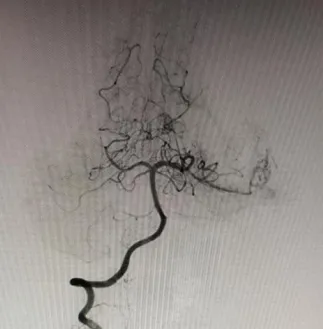

“叮鈴鈴,叮鈴鈴......”。凌晨一點,滄州市中心醫(yī)院神經(jīng)血管介入二科姜紅升醫(yī)生睡夢中被一陣急促的電話鈴聲吵醒,電話是某地縣醫(yī)院醫(yī)生打來的:一位高考完畢的18歲姑娘于夜間突然出現(xiàn)劇烈頭痛,伴惡心、嘔吐,隨后意識不清。這位患者被家屬送至當?shù)蒯t(yī)院,急查頭顱CT(圖一)示:左側(cè)顳枕葉腦出血破入腦室系統(tǒng),蛛網(wǎng)膜下腔出血。當?shù)蒯t(yī)院醫(yī)生隨即電話聯(lián)系姜紅升醫(yī)生并簡要說明了患者的基本情況。姜醫(yī)生了解相關情況后,依據(jù)患者為青年女性,既往體健,查體情況以及影像學結果提示,考慮腦動靜脈畸形破裂出血可能性大。姜紅升醫(yī)生、當?shù)蒯t(yī)院醫(yī)生同患者家屬緊急商議,最后家屬決定將患者轉(zhuǎn)至滄州市中心醫(yī)院腦科院區(qū)繼續(xù)治療?;颊咿D(zhuǎn)入滄州市中心醫(yī)院后完善查體:意識不清,精神差,反應遲鈍,刺痛可發(fā)音,雙側(cè)瞳孔正大等圓,對光反射遲鈍,頸項強直,刺痛四肢可動,巴氏征(-)。為預防腦疝形成,醫(yī)生們緊急對患者行“腦室外穿刺引流術”。 姜紅升醫(yī)生考慮,腦血管畸形出血情況不明下貿(mào)然手術可能會出現(xiàn)術中大出血、腦腫脹、畸形團位置不明確等嚴重后果,并且腦血管畸形存在著再次破裂出血、癲癇等可能性。遂向患者家屬交待行腦血管造影及視情況行介入治療的必要性?;颊呒覍俦硎局槔斫?,并同意造影及后續(xù)介入治療操作。姜紅升醫(yī)生遂于當日上午對患者行腦血管造影檢查。 患者造影結果提示:左側(cè)顳枕部動靜脈畸形,左側(cè)大腦后動脈顳后動脈分支主要供血,左側(cè)大腦中動脈少量供血,畸形團約2cm,通過橫竇引流。 了解造影結果后,姜紅升醫(yī)生與科室各位醫(yī)生對適合患者的治療方式進行討論:外科手術是當前治療腦血管畸形的主要方法,其優(yōu)勢在于根除病變部位,避免再次復發(fā);但手術前需要仔細研讀影像資料,了解畸形血管團生長的位置、大小、是否位于功能區(qū)、正確識別主要的供血動脈和引流靜脈等等,評估術中大出血、惡性腦腫脹、術后神經(jīng)系統(tǒng)功能缺損的風險,對手術方案的制訂和實施至關重要。介入治療創(chuàng)傷小,對于處理深部、功能區(qū)等手術無法切除的腦動靜脈畸形具有明顯優(yōu)勢;但介入治療相較于外科手術亦存在諸多不足:如不能達到治愈性栓塞,因改變畸形血管團的血流動力學,反而增加再次破裂出血的風險;栓塞材料的移位亦可能導致正常血管的閉塞,引發(fā)神經(jīng)功能障礙;以及介入治療后術后存在高復發(fā)率等等。本例患者畸形血管團位于非功能區(qū),其體積較小,合并顱內(nèi)出血,擬為患者行“介入栓塞+外科手術切除”治療策略:首先對腦血管畸形團供血動脈進行栓塞,降低畸形血管團血流量,從而大大降低后續(xù)外科手術切除過程中發(fā)生出血、腦腫脹的風險,提高外科手術的安全性,然后再對患者進行外科手術治療,達到根除病灶的效果。制訂出該患者治療策略后,姜紅升醫(yī)生對患者家屬充分交待病情以及手術方案,得到家屬的理解與同意。 團隊遂于介入導管手術臺上開始對患者畸形血管團進行介入栓塞,經(jīng)Marathons微導管向主要供血動脈及畸形血管團,分次注入Onyx膠。再次造影,提示畸形血管團殘余少量顯影,主要供血動脈消失,余血管未見異常。 栓塞術后待患者略恢復后,完善磁共振掃描等相關檢查,嚴密制訂手術計劃,于數(shù)天后行“腦血管畸形切除術”。顯微鏡下熒光造影,識別主要引流靜脈,確認后保護好引流靜脈,沿畸形血管團切除及清除顱內(nèi)出血,待完整切除動靜脈畸形團后,將引流靜脈電凝切斷。術后給予患者對癥治療,經(jīng)過積極治療,患者恢復良好,未遺留明顯后遺癥,順利出院。 在患者出院后,姜紅升醫(yī)生也收到了該患者被大學錄取的喜訊。出院后的患者即將迎來嶄新美好的大學生涯。 溫馨提示 年輕、既往無高血壓病史患者,如出現(xiàn)腦出血,務必考慮到腦血管畸形的可能性,盡量爭取機會完善相關檢查,確定患者腦出血的病因,并根據(jù)患者實際情況,嚴密制訂合理的治療策略。如貿(mào)然為患者行顱內(nèi)血腫清除術,可能會導致術中大出血,惡性腦腫脹等惡性事件,導致患者出現(xiàn)致死致殘的災難性后果。